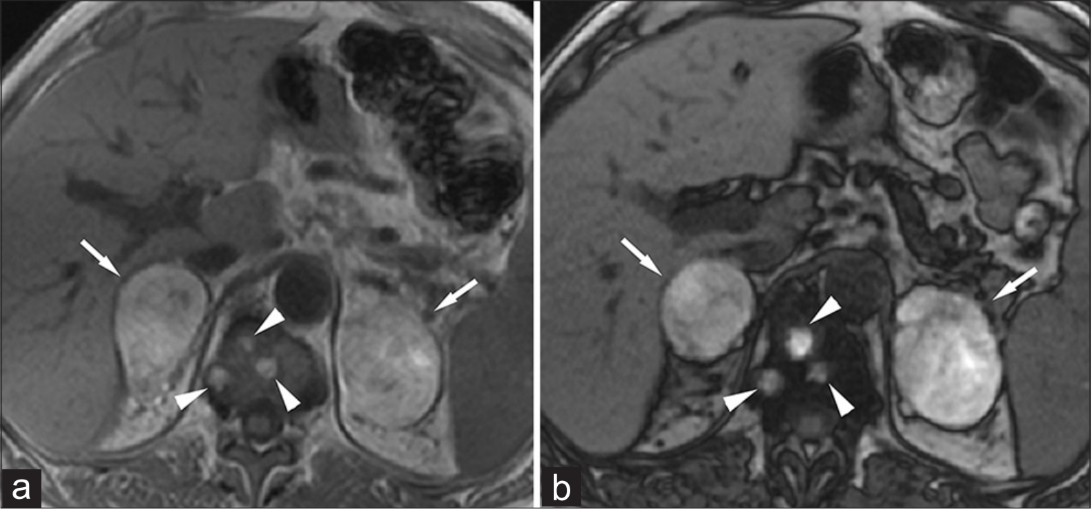

Phaeochromocytomas are tumours originating from the adrenal medulla and often produce excess adrenaline. They are classically bright on T2-weighted MRI images, the so-called “light bulb” sign, and enhance strongly after contrast24.